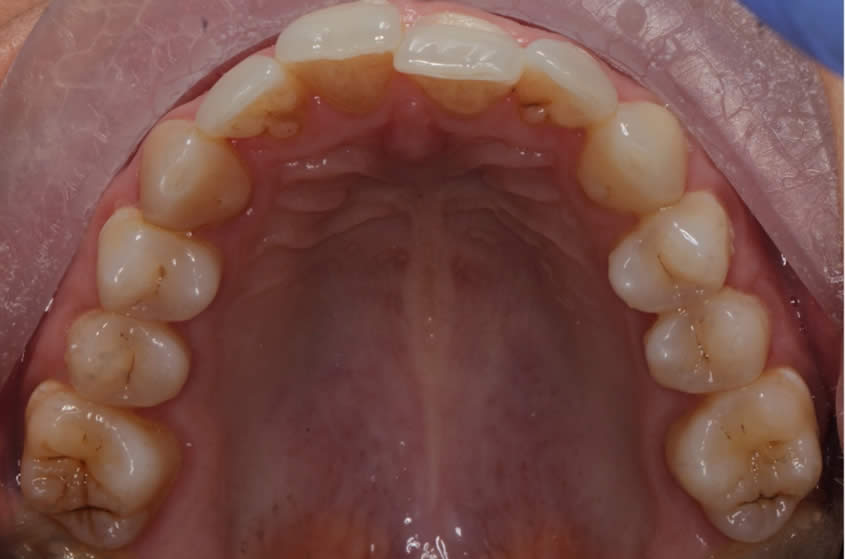

Patient Teeth Straightening Case

Teeth Straightening - Case 2